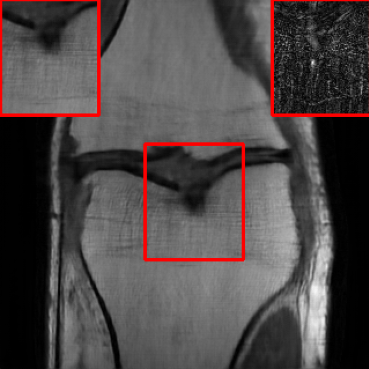

Figs. 4 and 5 show images reconstructed by different methods at 8x and 4x undersampling, respectively. The LONDN-MRI reconstructions (either iterative or oracle) show fewer artifacts, sharper features, and fewer errors than the global MoDL and initial aliased reconstructions. The iterative LONDN-MRI results are also quite close to the oracle result.

| Ground Truth | Global | LONDN-MRI | LONDN-MRI | Oracle |

| (1 iteration) | (2 iterations) | |||

![]() |

| PSNR = dB | PSNR = 32.78 dB | PSNR = 33.16 dB | PSNR = 33.25 dB | PSNR = 33.30 dB |

| Initial | DIP | SOUP-DIL | RAKI | LORAKI |

| PSNR = 21.23 dB | PSNR = 30.18 dB | PSNR = 30.66 dB | PSNR = 31.26 dB | PSNR = 31.67 dB |